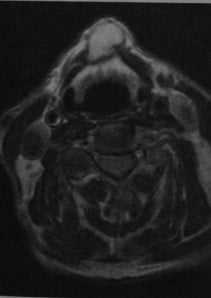

Щитовидно-язычная киста. МРТ, Т2-взвешенное изображение: киста с четкими границами, расположенная сразу под подъязычной костью с гиперинтенсивным содержимым и гипоинтенсивной стенкой. Киста образует определяемую визуально выпуклость кожи.